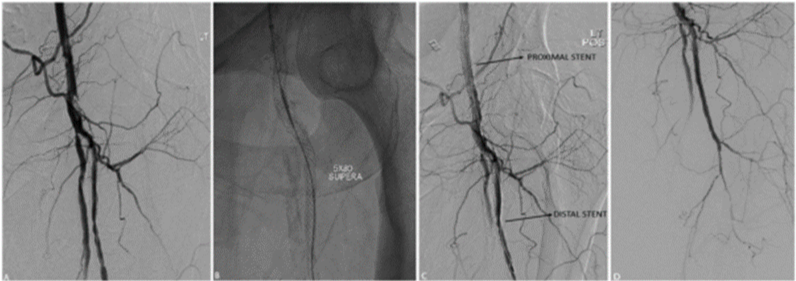

图4. 单支架,独立的股总动脉。初始造影:股总动脉中度狭窄,伴股浅动脉近端严重狭窄(A)。股总动脉8mm球囊预扩,随后植入7mm×40mm SUPERA支架(B)。造影结果良好(C)

图片

图5. 对吻支架。91岁女性CLI,初始造影:股浅和股深动脉起始段高度狭窄(A),植入2枚SUPERA支架(均为4mm×40mm),以对吻方式跨过分叉病变(B,C),显影改善(D)